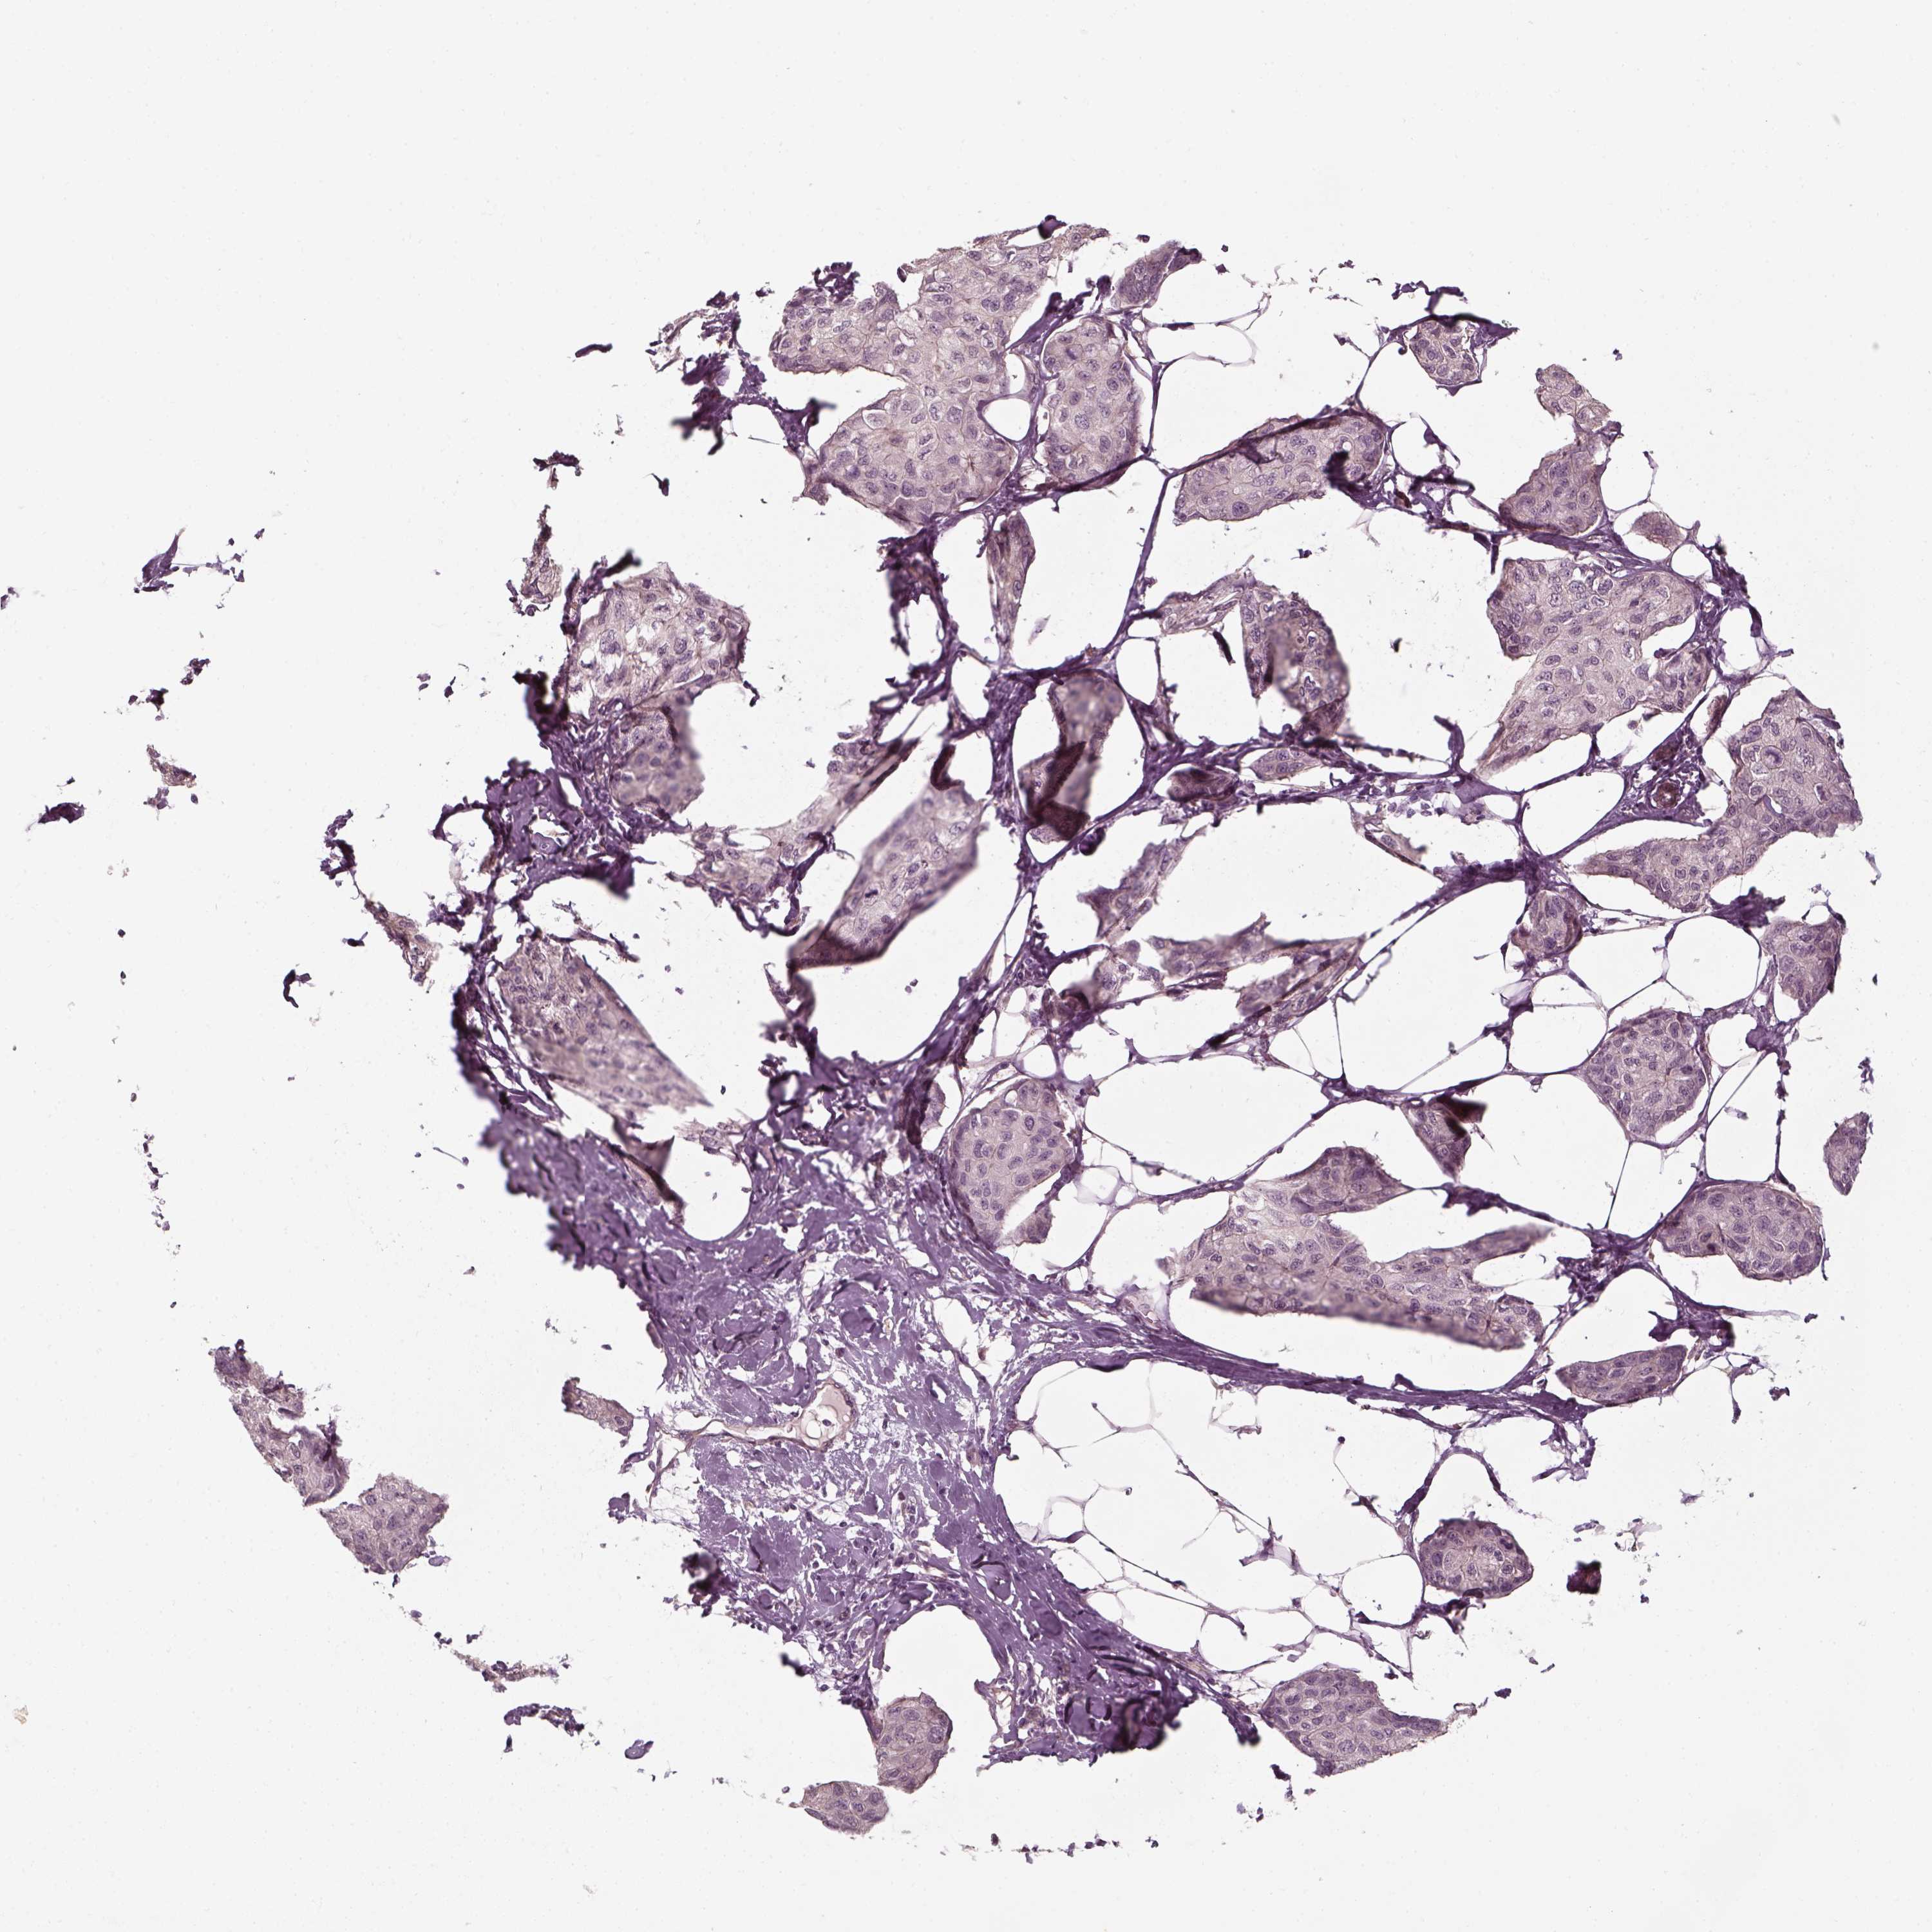

CANCER BREAST CANCER Show tissue menu

BRCA TCGA BRCA VALIDATION PROTEIN EXPRESSION

Breast cancer

Human cancer